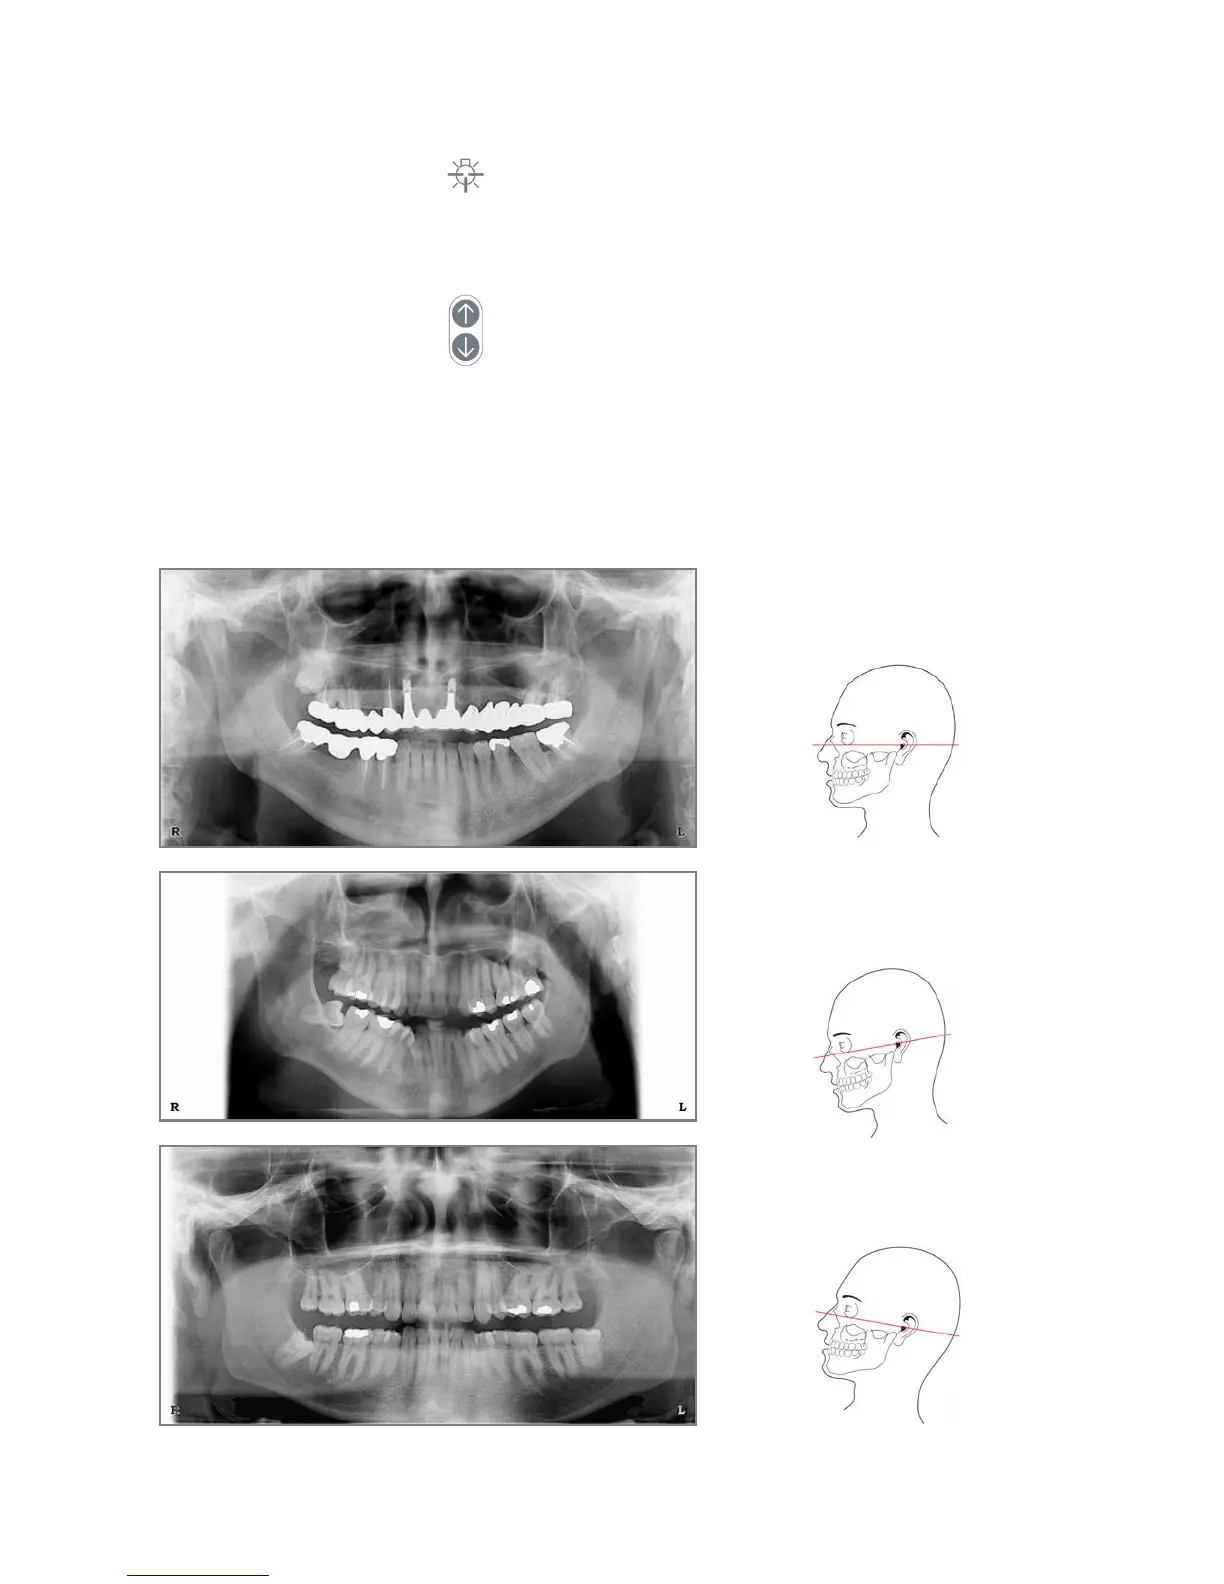

Correct position:

Frankfurt plane is horizontal.

Wrong position:

Frankfurt plane is NOT horizontal

The head is tilted forward thus

resulting in a V shaped dental arch.

The head is tilted backward, thus

resulting in a flat dental arch.